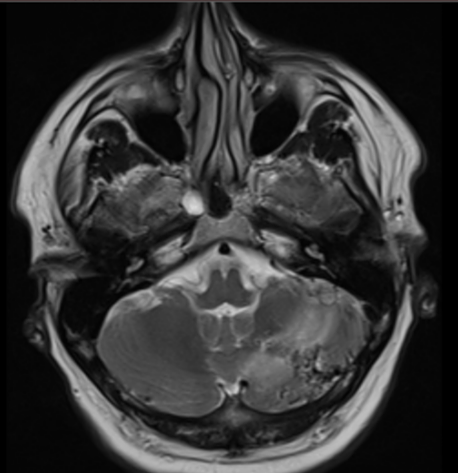

Figura 1: imagine din achiziţie oblic axială la nivelul fosei posterioare; se evidențiază o malformaţie arterio-venoasă cerebeloasă stângă: se remarcă atât nidusul malformației cât şi efectul asupra parenchimului cerebral prin prezența unei plaje cortico-subcorticale în hipersemnal T2.